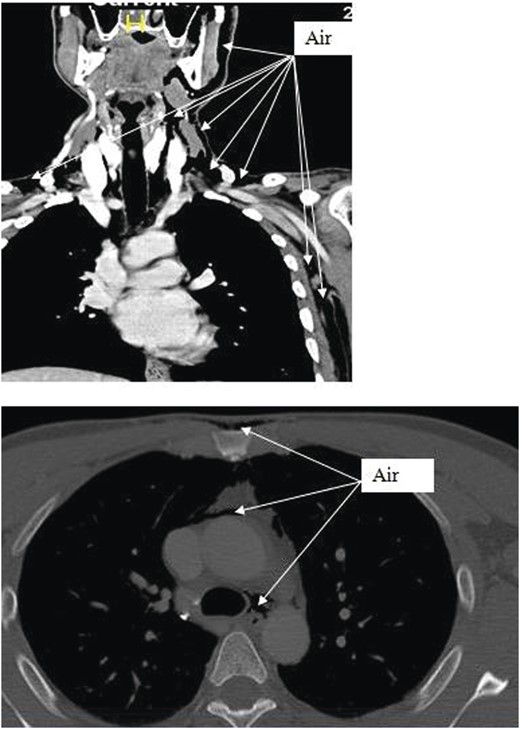

Chest X-ray and head, neck and chest computed tomography (CT) confirmed the diagnosis and extension of PM (Figs 1–3). CT revealed fracture of the floor of left orbit with soft tissue, fat herniation into left maxillary sinus roof, left orbital emphysema with no muscular entrapment. Gas was observed in periorbital tissues, left temporal scalp, infratemporal fossa, left parapharyngeal space and left cheek. Moreover, tissue planes in the neck revealed the presence of air particularly around the carotid vessels, in the posterior triangle and superior mediastinum (PM) around the thymus, trachea (middle), left side of the aorta and anterior to the sternum. However, on auscultation, lungs were clear with and the laryngeal passages and trachea looked normal.

Different levels of head imagining showing fracture of the floor of the orbit and subcutaneous air.

CT scan shows the extension of air from the face, neck and chest.